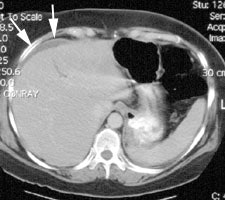

Bile Leak: The post-cholecystectomy patient shown below was being evaluated for abdominal pain and fever. The CT scan demonstrated a fluid collection anterior to the liver (white arrows- click CT image to enlarge). A hepatobiliary study demonstrated a bile leak. Increasing tracer activity can be seen over the liver corresponding to the fluid collection on the CT scan. Bile can also be seen pooling in the gallbladder fossa and extending down the right paracolic gutter. |